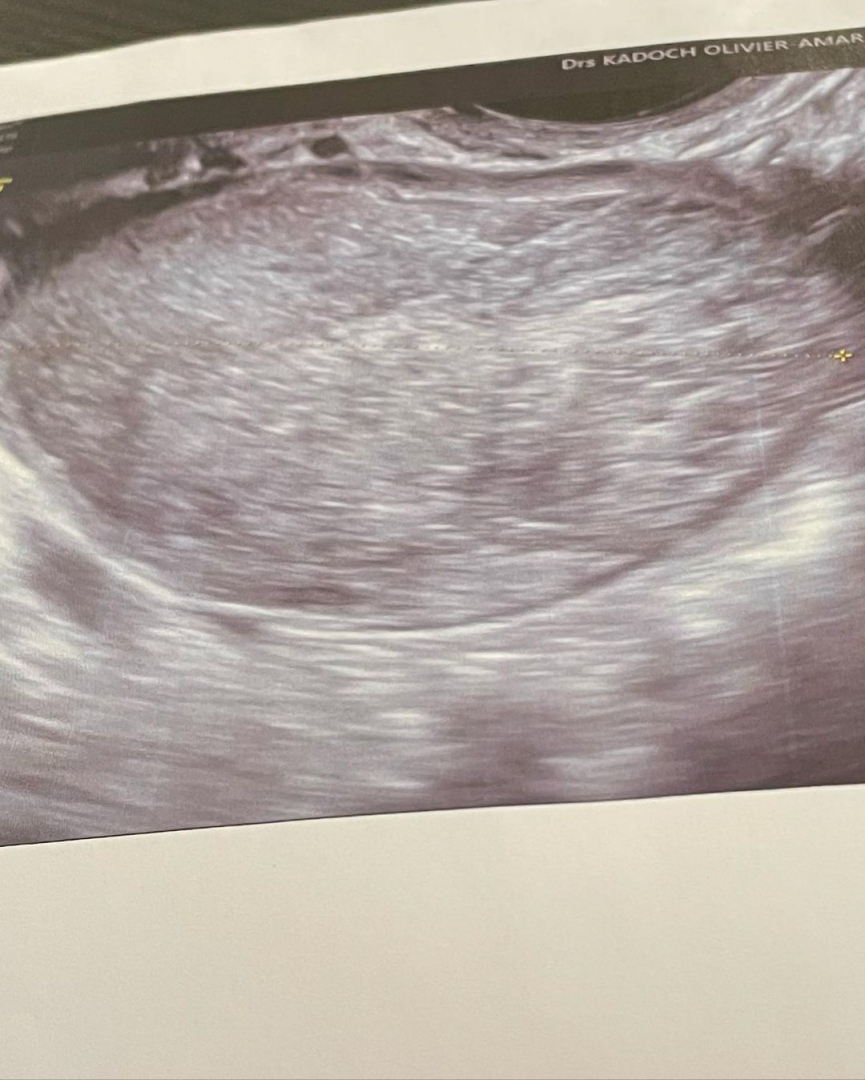

Thylane Blondeau a publicat pe rețelele sociale, imagini realizate pe patul de spital, mărturisindu-le fanilor că a fost operată de urgență, după ce un medic i-a descoperit un chist ovarian de peste 5 centimetri. Înainte de operație, Thylane a avut parte de un adevărat periplu prin spitale, după ce mai mulți medici nu i-au identificat încă de la început problema. Ea a menționat că „nu era sigură dacă să posteze sau nu” mesajul, însă în cele din urmă a hotărât să povestească totul.

Ea a precizat că în ziua următoare a avut de-a face cu un medic care i-a descoperit un chist de 5,6 centimetri și care a operat-o de urgență.